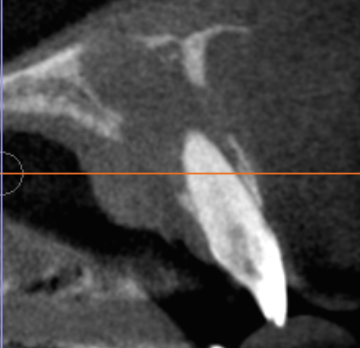

診断の要点|CT(CBCT)で「病変の正体と広がり」を立体的に評価

前歯部はレントゲンでは病変が重なって見えやすく、

「根の感染が主体なのか」

「嚢胞が主体なのか」

「両方が関与しているのか」

が判断しにくいことがあります。

当院ではCT(CBCT)で病変の範囲と位置関係を把握し、

根管治療で解決すべき領域と

外科的に対応すべき領域を分けて治療計画を作ります。

術後経過|3ヶ月で骨の回復(骨形成)を確認

術後3ヶ月の画像で、骨ができてきている所見(骨形成)を確認しています。

骨は時間とともに成熟していくため、今後も定期的に経過を追い、再感染や咬合(噛み合わせ)も含めて長期予後を評価していきます。